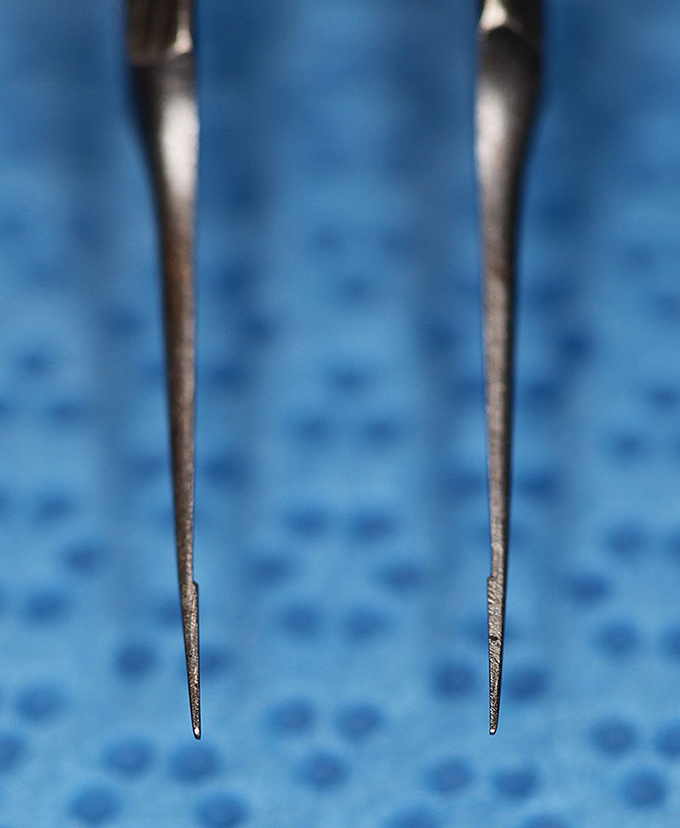

Forcep Thumb, Utrata (Enlarged)

(aka Utrara Forceps)

catalog number: Storz 2-719

Typical Use(s): Capsulorhexis; Remove stuck haptic from IOL optic